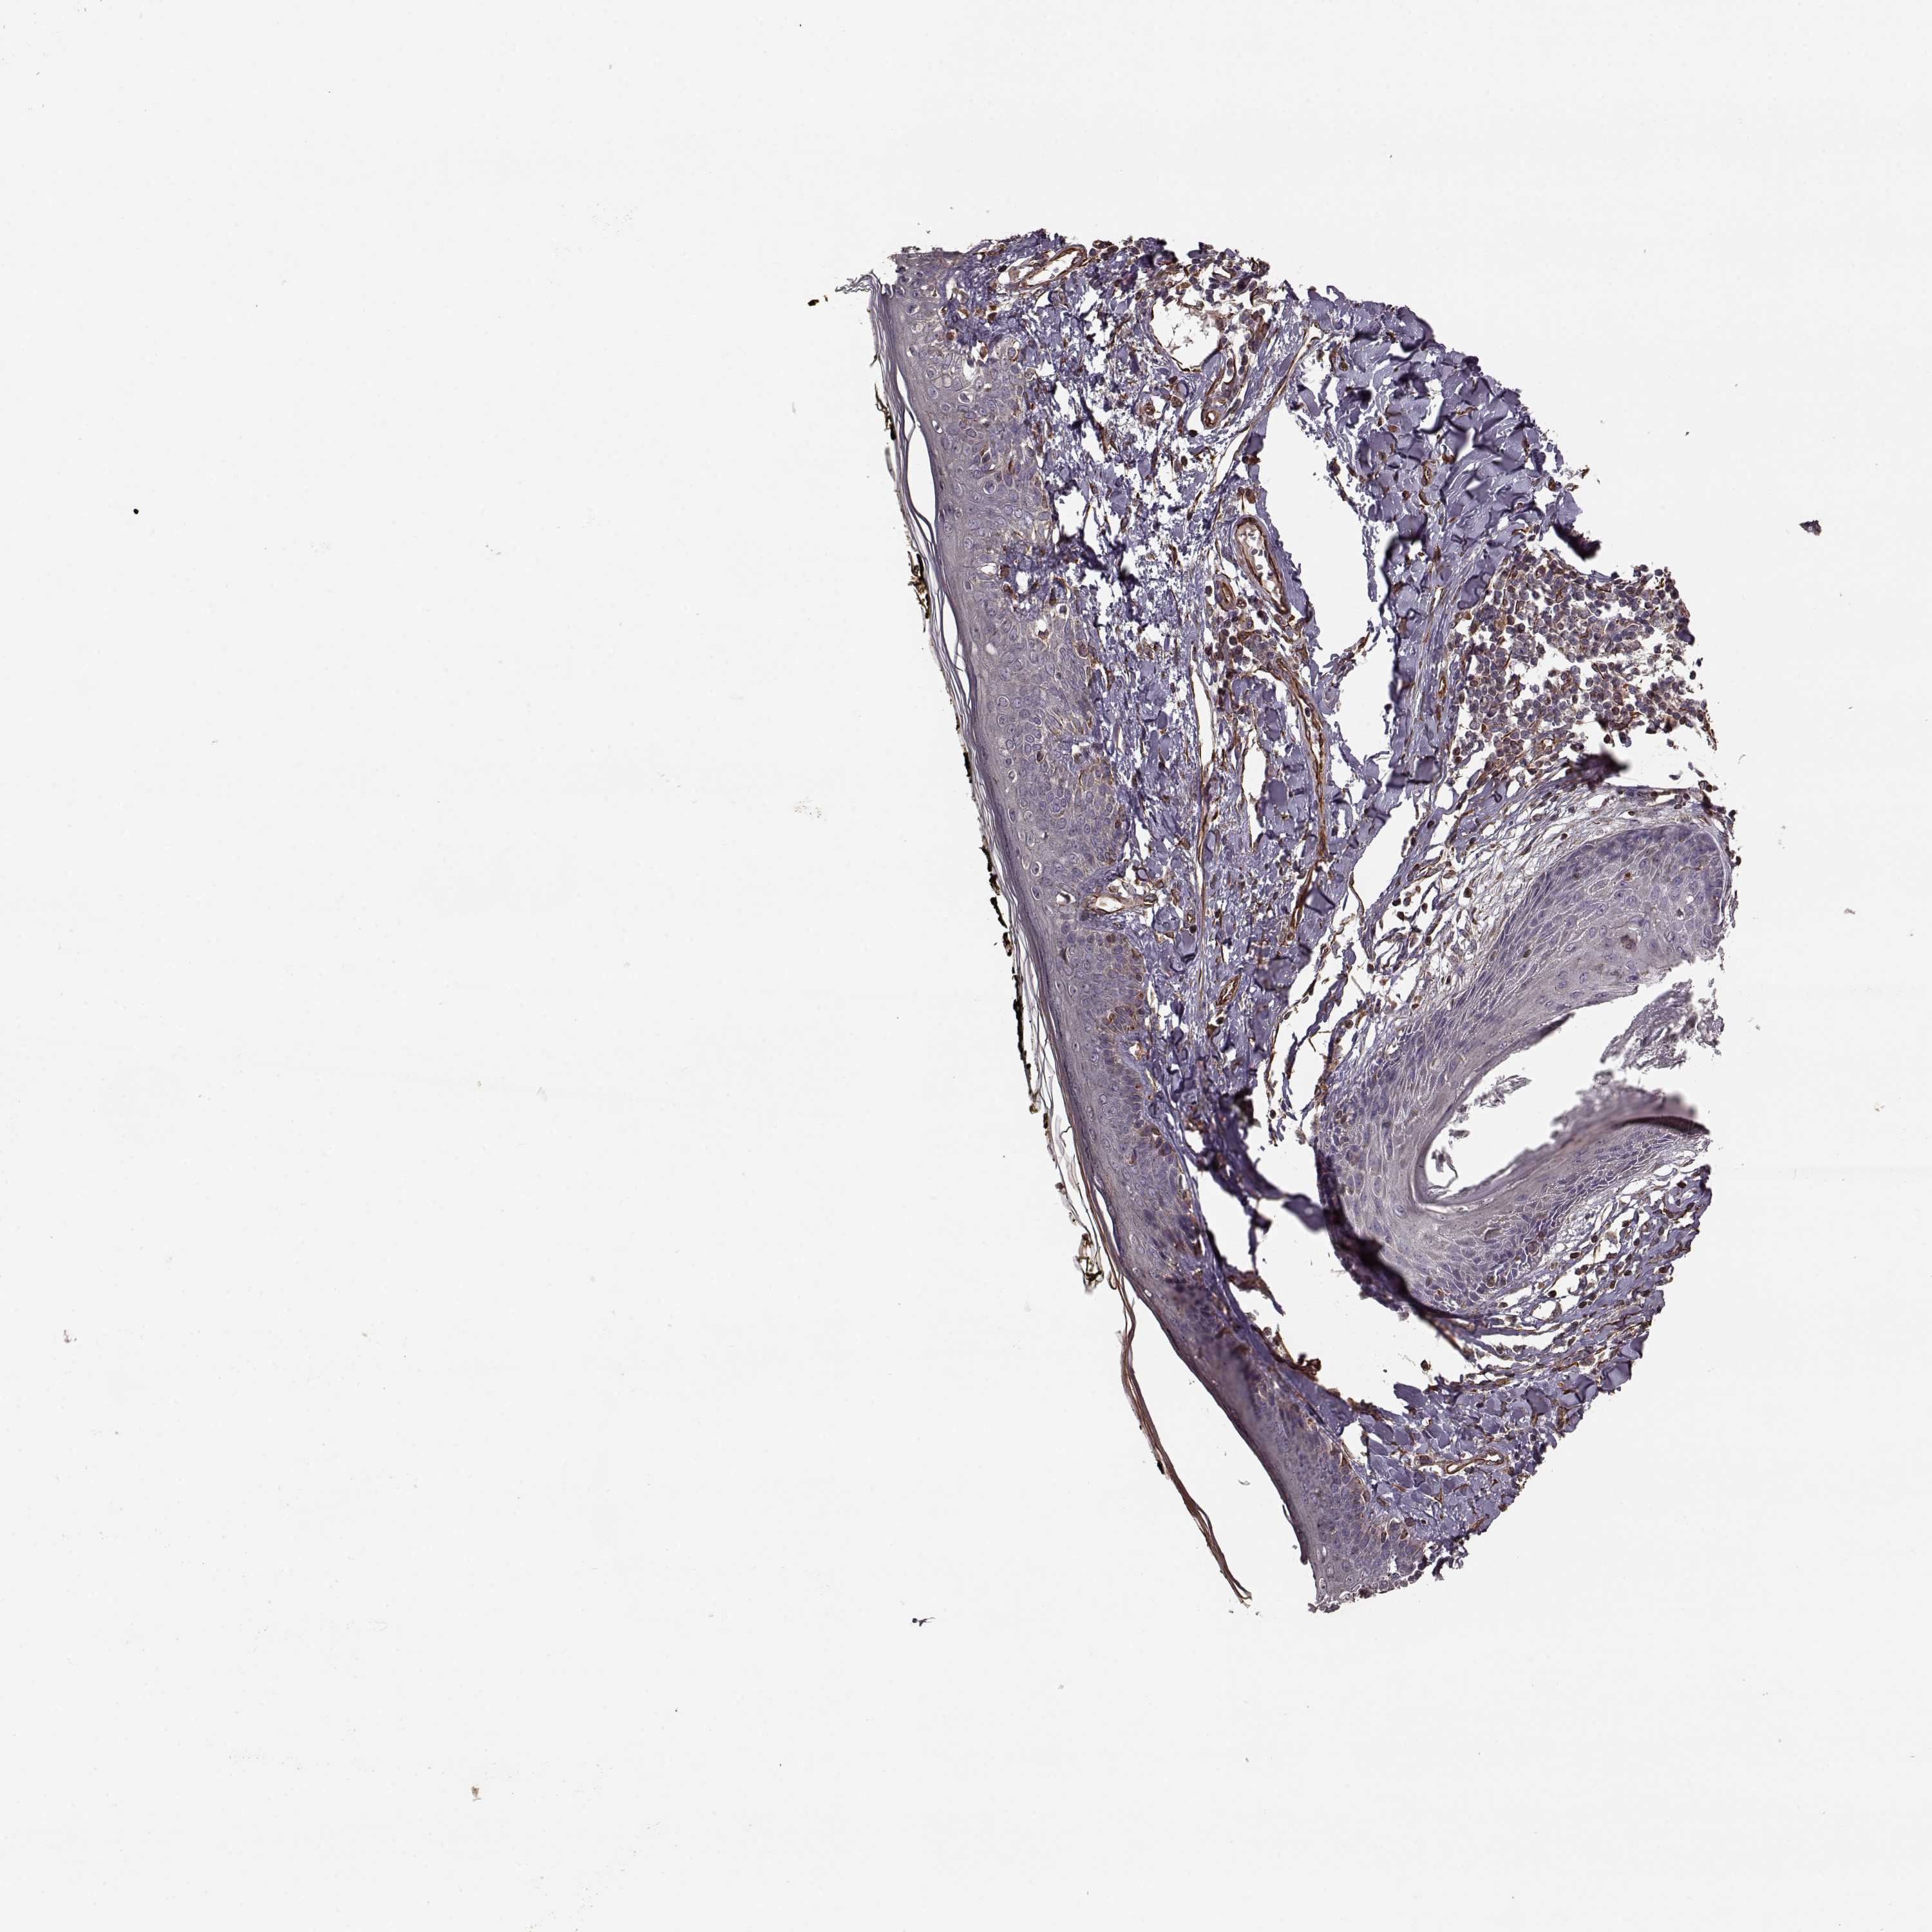

SKIN 2 - Antibody stainingi

Antibody staining in the annotated cell types in the current human tissue is reported as not detected, low, medium, or high, based on conventional immunohistochemistry profiling in selected tissues. This score is based on the combination of the staining intensity and fraction of stained cells.

Each image is clickable and will lead to virtual microscopy that enables deeper exploration of all samples and also displays staining intensity scores, fraction scores and subcellular localization as well as patient and tissue information for each sample.

Antibody HPA032001

Epidermal cells Not detected